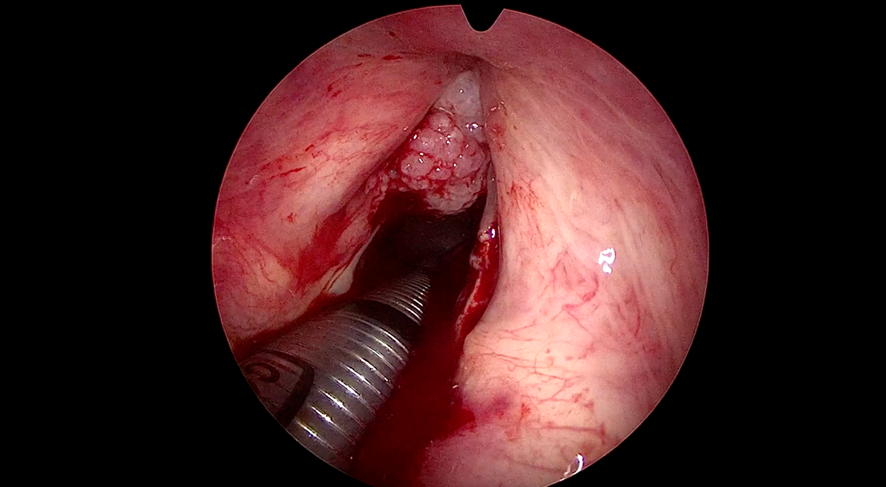

Assim como acontece com o câncer da tireoide, em que a cirurgia passa a ser o tratamento assertivo, sem a necessidade de complementação com quimioterápicos e radiação, no câncer de laringe, para alguns casos, está indicado a ressecção a laser, a cirurgia endoscópica a laser. Eu, particularmente, gosto da ressecção a laser. Quando bem indicada evita a radioterapia, que por vezes é uma opção nos canceres da laringe. A Radioterapia tem mais efeitos colaterais do que a cirurgia a laser isoladamente.

As principais vantagens do laser são a recuperação rápida e o retorno às atividades cotidianas e à vida social. Na maioria dos casos, esse tratamento não requer o uso da traqueostomia! Outro ponto favorável desta técnica cirúrgica é o menor risco de sequelas, com índices positivos de preservação da voz.